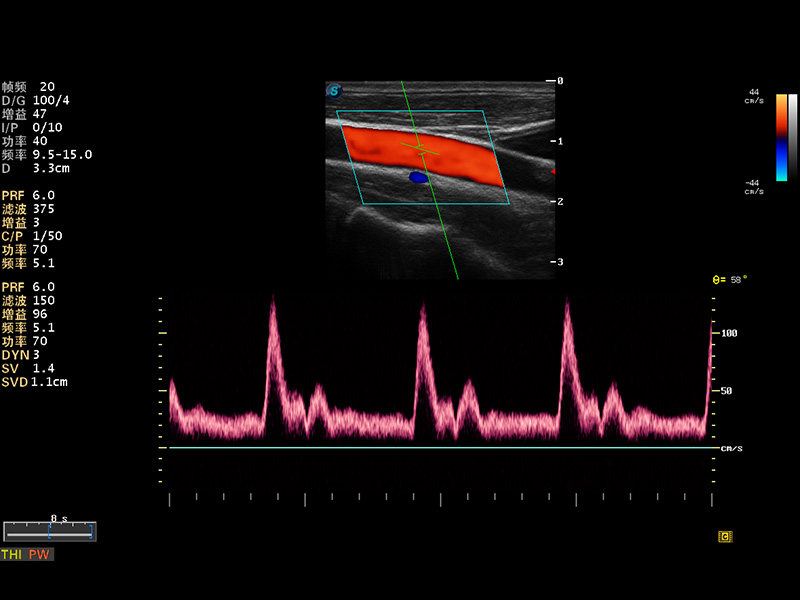

S8 EXP便携式彩色多普勒超声诊断仪是乐玩lewin国际研发的高端全身应用型便携彩超。高通道的VIS平台融合可视化(Visual)、智能化(Intelligent)和人性化(Smart)的特点,配以乐玩lewin国际自主研发生产的探头大家族,使您能够快速、准确的获得病人信息,提高工作效率的同时减轻疲劳。

成像技术

多波束形成器